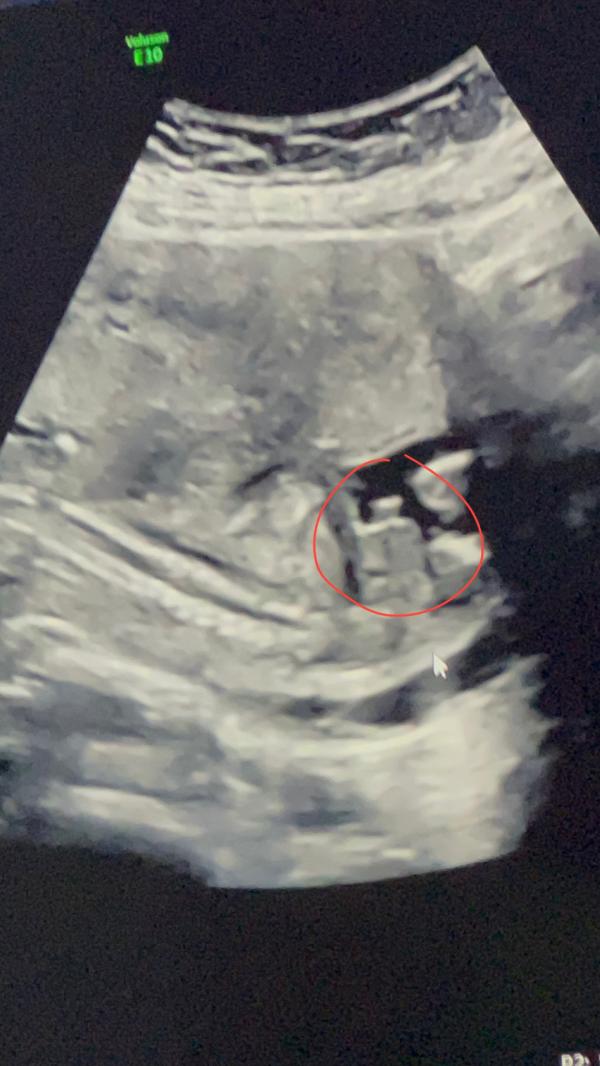

Подтвердили что мальчик

Пипку тоже показали😂🫶🏼